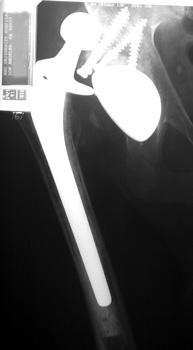

Dislocated femoral component related to non union of greater

trochanteric osteotomy. Post operative radiograph with constraining ring about

femoral head, which helps maintain head in cup. Greater trochanter resected.